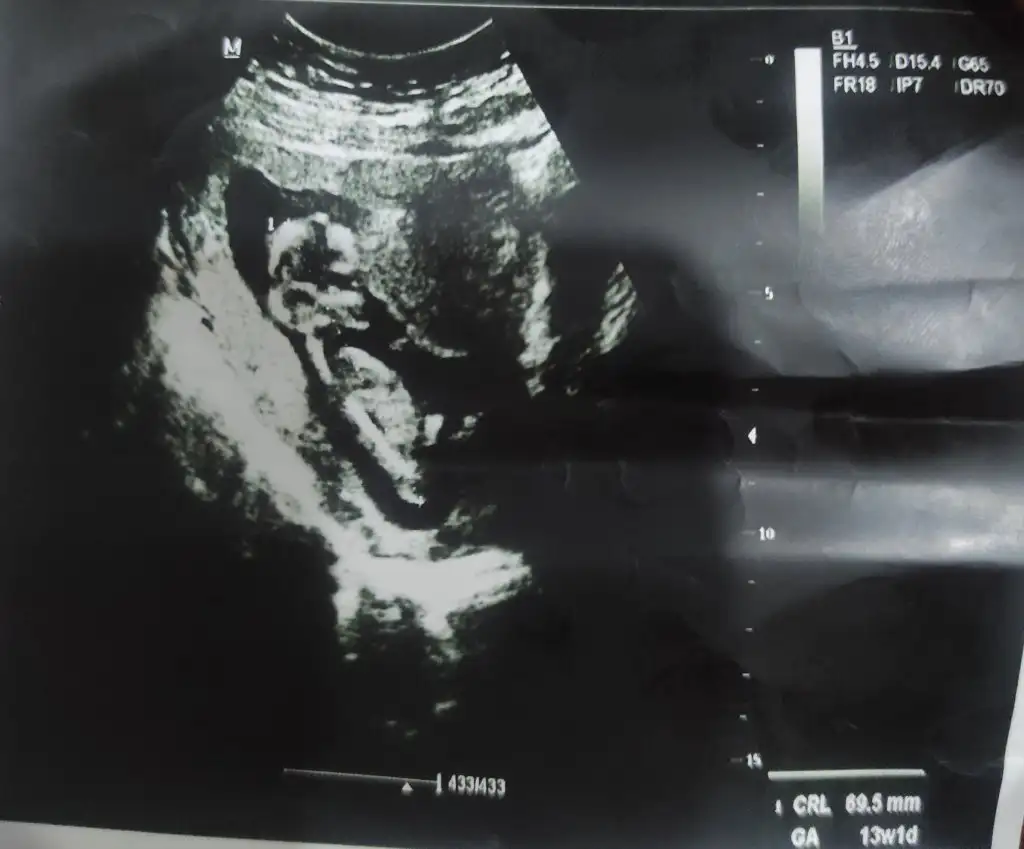

Merhaba arkadaşlar. İki hafta önce kanamam olmuştu. Doktora gittiğimde bir sorun yoktu ama 10 gün rapor yazdi. Bugün yine doktora gittim. Bu iki haftalık sürede birkaç defa koyu lekeler görmüştüm. Bir de rahimin biraz altında ağrılarım oluyor. Doktor rahim genişlemesinden mi yok düşük tehlikesinden mi bilmiyorum dedi ve 7 gün daha rapor yazdı. 13+1 olmuşuz ve günümüz uyumlu. Boyumuzda 6.9 olmuş. Doktor ultrasonda yine bir sorun görünmüyor dedi. Benim gibi rahimin hemen alt tarafında ağrısı olan var mı? Bir de doktor erkeğe benziyor dedi ama emin degilim diye ekledi. Burda hep erkek diye yorum yapıldı. Bu görüntüye göre hala erkek diyor musunuz :)

Geçmiş olsun canım, bol bol dinlen. Umarım bundan sonrası sorunsuz geçer ve ben hala erkek diyorum 🥰